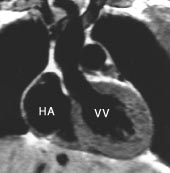

T1-vektede MR-bilder viser det normale perikard som en mørk stripe mellom to lyse vev, det epikardiale fettvev og det perikardiale fettvev (fig 8, 9). Fortykkelse av perikard ( ≥ 4 mm) kan av og til sees ved akutt perikarditt, men er mer vanlig ved kronisk perikarditt. MR er en sensitiv metode til å påvise konstriktiv perikarditt (20). I tillegg til perikardfortykkelsen, sees dilatasjon av høyre atrium, v. cava inferior og levervenene og normalt stor eller liten høyre ventrikkel. MR er imidlertid en dårlig metode til å påvise forkalkninger i perikard. Perikardvæske har et varierende utseende ved MR avhengig av innhold av protein og andre makromolekyler. Stormolekylære stoffer forkorter væskens T1 og forårsaker økt signalstyrke på T1-vektede bilder. Eksudatet i perikard ved den sterkt inflammatoriske uremiske perikarditt gir således et moderat kraftig signal på T1-vektede bilder, mens det perikardiale transsudat som sees ved f.eks. hjertesvikt, har nesten manglende signal på T1-vektede bilder (fig 7). Hemoperikardium har et karakteristisk utseende med en intens signalstyrke på T1-vektede bilder.